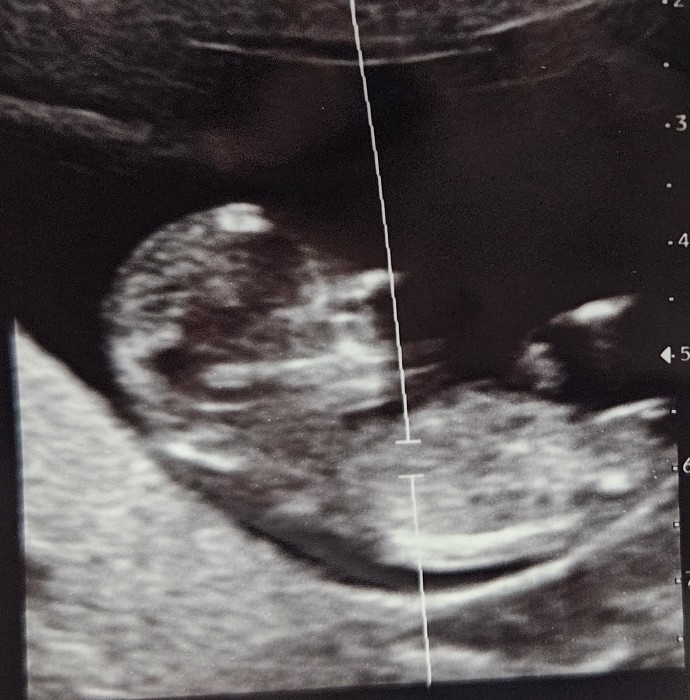

11주 초음파 성별 예측이 될까요?ㅎㅎ

넘 궁금해요 ㅎㅎ

딸인거같아요~

딸~~?? 같은데!!